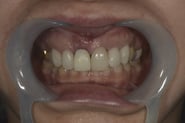

Simplified Microscopic Implant surgical Lifelike Esthetics を略した手術名で、米国カルフォルニア州サンタバーバラで歯周病専門医として開業されていた、 Dr. Dennis Shanelec(故人)が考案した治療法です。抜歯した直後に仮歯を入れることによって,歯を取り巻く骨(硬組織)や歯肉(軟組織)の状態を維持できる非常に優れた方法です。しかし、手術としての難易度は非常に高いレベルに位置づけられます。

抜歯した直後にインプラントを埋入し、仮の歯を作製、唇側の骨のボリュームを保つために人工骨と結合組織を同時に移植する非常に優れた方法です。